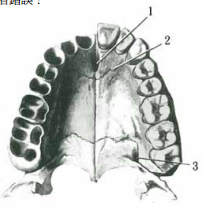

4 關於下圖所示,下列敘述何者錯誤?

(A) 1 為門齒管(incisive canal) (B) 1 管道中含有史坦生器官(the organ of Stensen) (C) 2 為腭骨(palatine bone)與上顎骨所形成之骨縫 (D) 3 管道中含有前腭神經及血管(anterior palatine nerve and vessels)